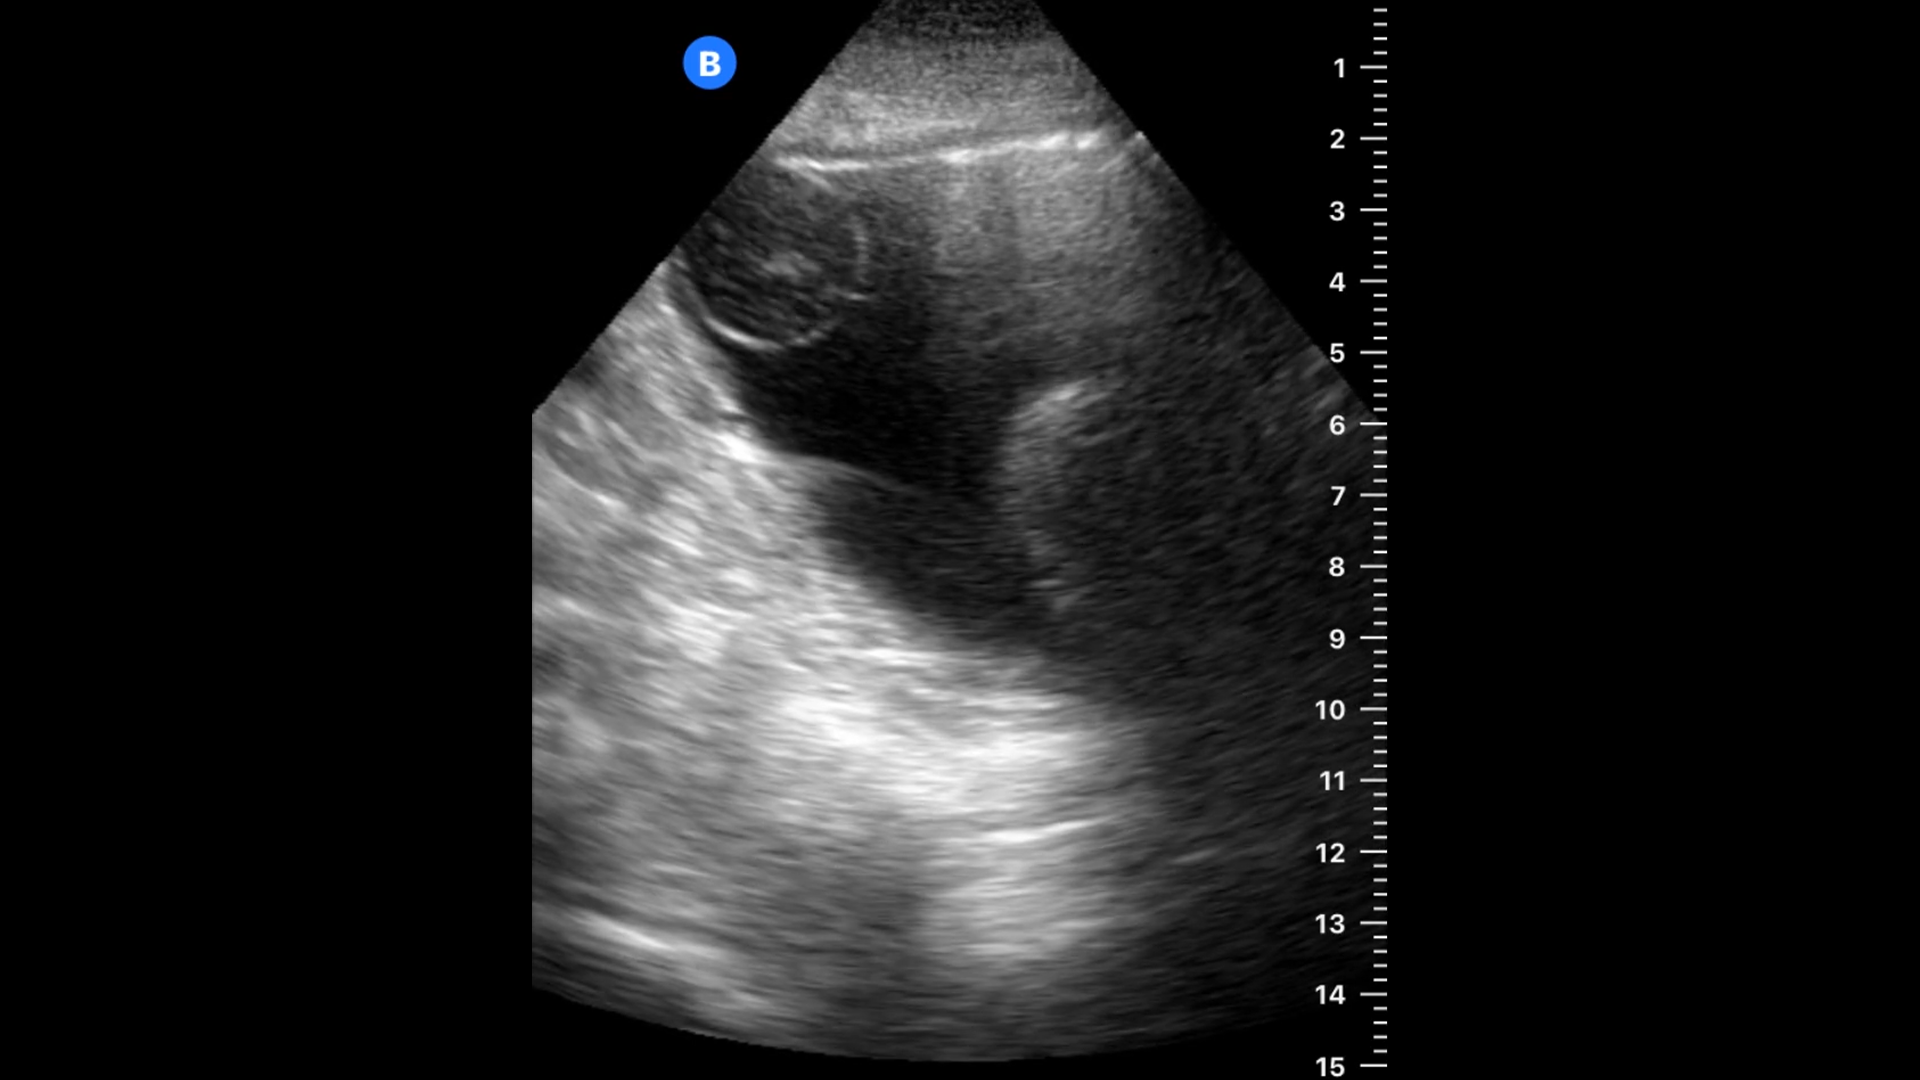

A 74 year-old man who presented with pain and bleeding into the bag after a Foley catheter had been placed at an outside clinic for urinary retention. Our first concern was whether the catheter was in the bladder or obstructed.

Here we see the images on arrival. (All of these images are in long axis – probe marker towards the patient’s head.)

It’s clear from the images that the catheter was not fully inserted before the balloon was inflated. In this case, the tip appears to be within the bladder; so it is likely that there was urine obtained prior to the inflation, which usually is an indication that catheter is in the proper place.

Based on these images, the balloon was deflated and the catheter advanced. Once it was seen to be within the bladder, the balloon was reinflated and the following image was obtained.